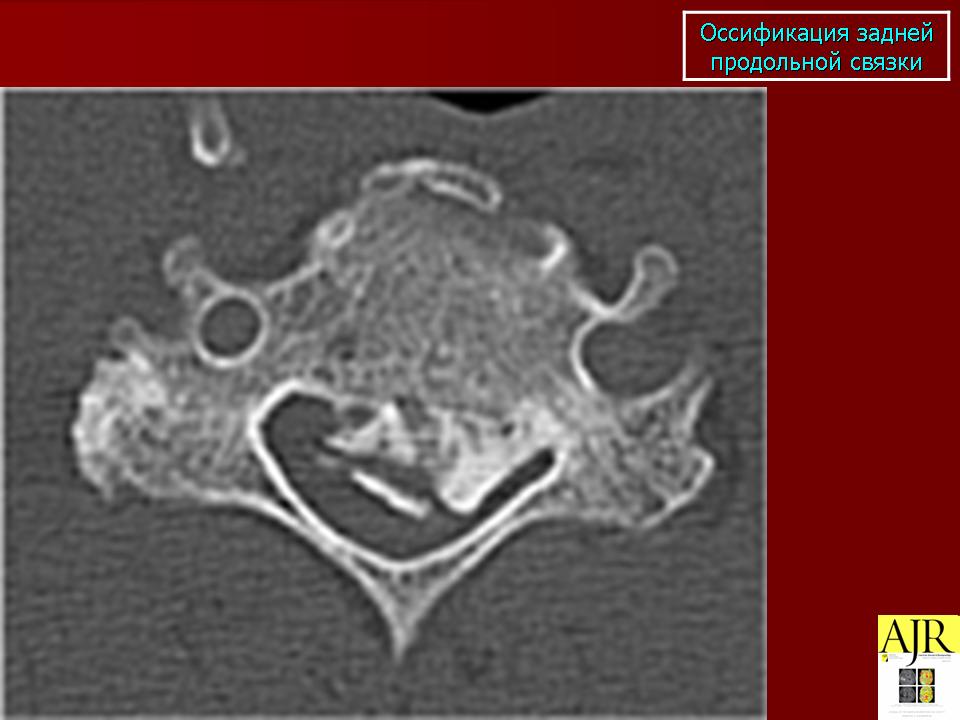

КСС. Оссификации. +

Оссификации.